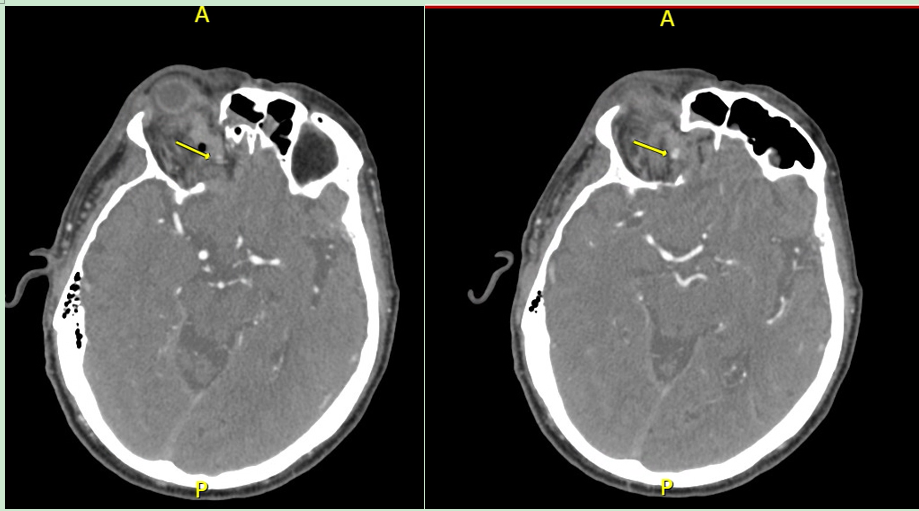

This is the Initial CT Head Angiogram that captured OAPA (red arrow): Patient on warfarin initially presented to the ED after tripping and falling with positive head strike against cement pavement. Trauma team noted pulsatile hematoma and proptosis of the right orbit. OAPA started to appear 24 hours after initial resuscitation at the trauma bay. Note patient also had a subdural hematoma with midline shift. Radiology noted 2 small foci of contrast in the right superomedial orbit with possible active extravasation.